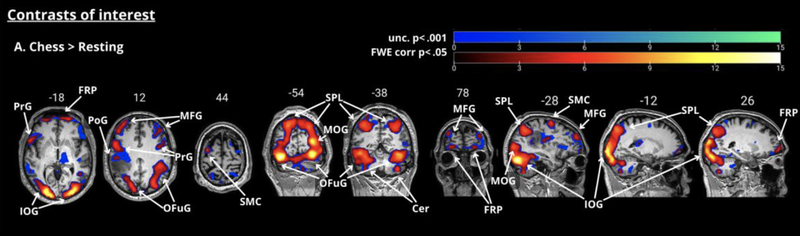

The image below shows you the network of regions you get when you look for parts of the brain that were significantly more active during any/all of the chess tasks (Conditions B-D all summed together) compared to the Resting condition. If it looks complicated - it is! Remember that this represents all the different things that are happening when AB carries out those chess tasks and that aren't happening when he's just staring a small plus sign for about 12 seconds. He's seeing colors and shapes (hello there, visual cortex!), he's making decisions about what to respond (looking at you frontal lobe and maybe some pre-motor cortex) and he's doing whatever spatial reasoning he needs to do to assess checkmating patterns and move legality. Where is chess in AB's brain? Kind of all over the place!

Figure 6 (adapted from Cepero-Escribano et al., 2024) - A contrast between all of the chess tasks administered in the scanner to AB and a baseline rest condition. The substantial differences between playing chess and doing nothing mean that a sprawling network of active brain areas is evident here.